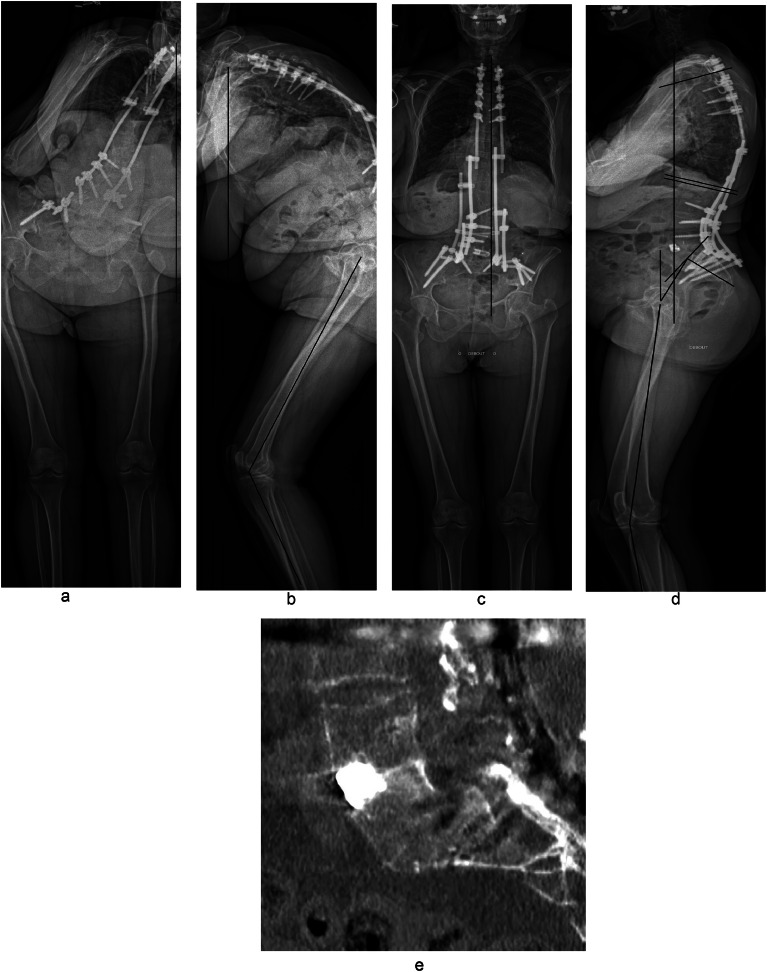

Fig. 7.

Sixty seven y old patient with multiple previous surgeries. Preoperative full spine anteroposterior and lateral X-ray showing severe sagittal and coronal malalignment to the extent that the patient could not fit completely inside the EOS cabin's field, which illustrates the limits of the imaging system in such cases (A and B) with difficulties to measure pelvic parameters and LL, C7-CSVL>10 cm, SVA>10 cm, knee flexion=49° Postoperative full spine anteroposterior and lateral X-ray after L5 PSO demonstrating significant improvement of the patient's global alignment including knee flexion compensatory mechanism, a cage was inserted anteriorly inside the L5 osteotomy site (C and D), C7-CSVL=2 cm, PI=80°, PT=29°, SVA=4 cm, LL=−70°, TK=36°, knee flexion=13° Postoperative CT scan at 2 years illustrating clear fusion posterior to the cage with bony contact between L4 and L5 (E).